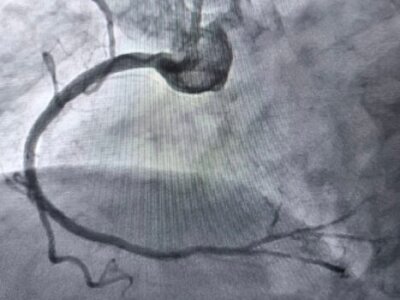

У таких ситуаціях на допомогу приходить ротаблятор – спеціальний пристрій із буром, покритим діамантовим напиленням. Він дозволяє «модифікувати» кальциновану атеросклеротичну бляшку, фактично шліфуючи її та відновлюючи можливість для подальшого стентування судини. Саме таким методом лікарям вдалося ліквідувати перешкоду в артерії та успішно імплантувати стенти.

«Це втручання стало важливим кроком для нашої лікарні та всієї області. Ротаційна атеректомія застосовується у найскладніших випадках кальцинованих уражень коронарних артерій, коли стандартна ангіопластика неефективна. Виконання такої процедури означає, що пацієнти Тернопільщини можуть отримати сучасну високоспеціалізовану допомогу без необхідності їхати в інші регіони», – наголосив Богдан Маслій.